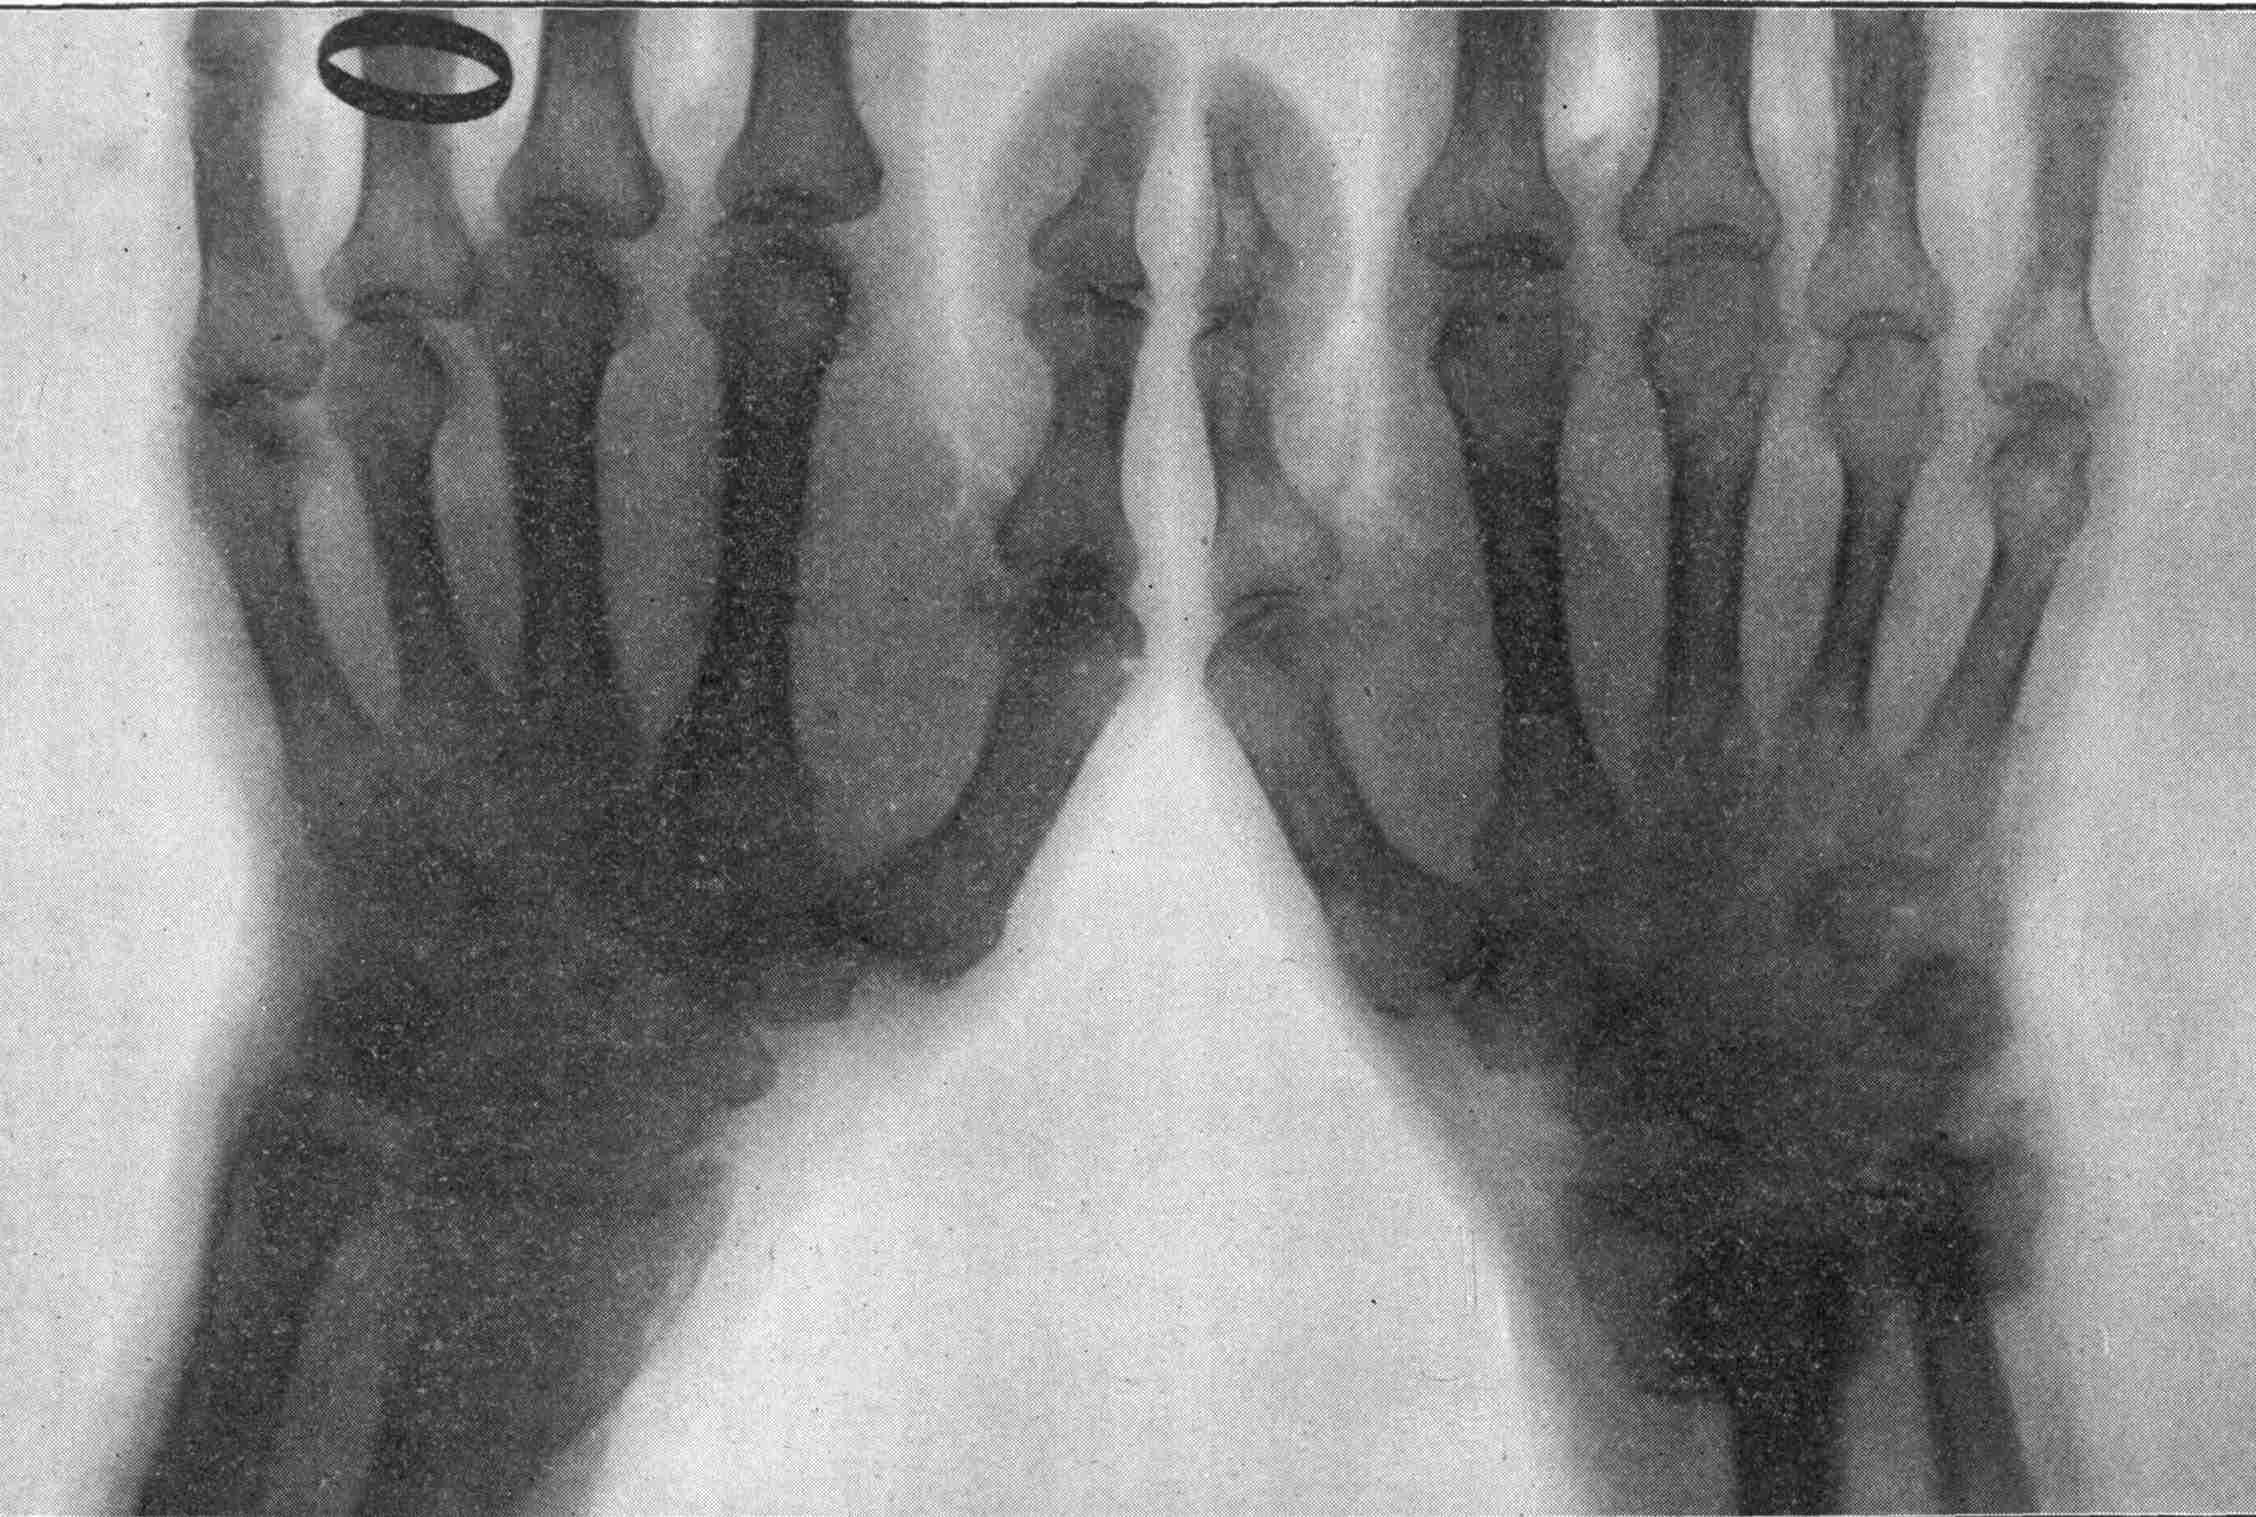

Fig. 1.—Head.

Fig. 2.—Broken Arm, Overlapping.

(Due to defective setting.)

Fig. 3.—Ribs.

Fig. 4.—Knee, Knickerbocker Buttons, Bullet in Femur.

FROM SCIAGRAPHS BY PROF. DAYTON C. MILLER. § 204.